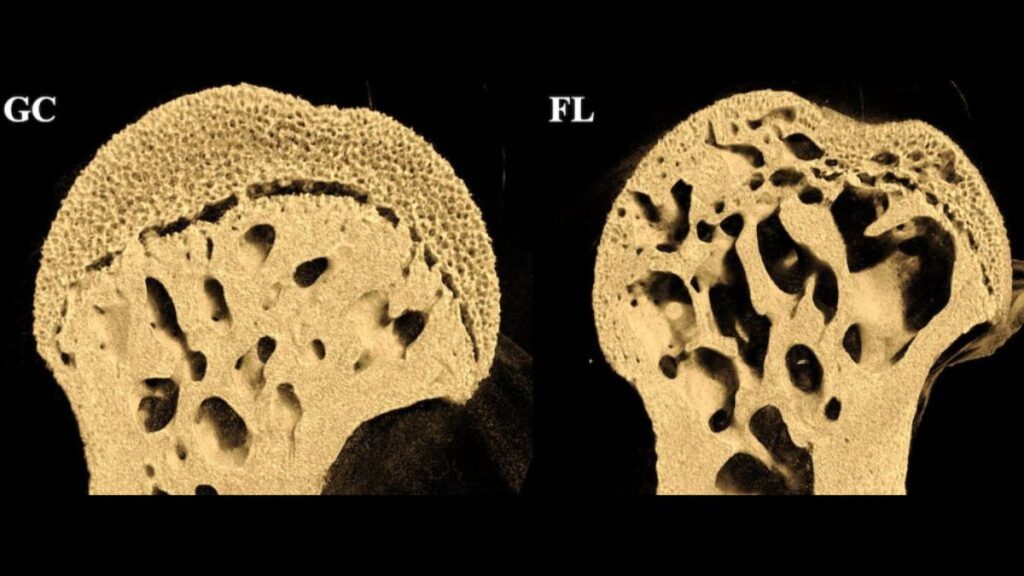

La NASA a envoyé des souris dans l’espace, elles sont revenues avec des trous dans les os

Les souris qui ont été envoyées dans l’espace ont subi une importante perte de densité osseuse, notamment dans les parties inférieures de leur corps. The post La NASA a envoyé des souris dans l’espace, elles sont revenues avec des trous dans les os appeared first on Daily Geek Show.

Les souris qui ont été envoyées dans l’espace ont subi une importante perte de densité osseuse, notamment dans les parties inférieures de leur corps.